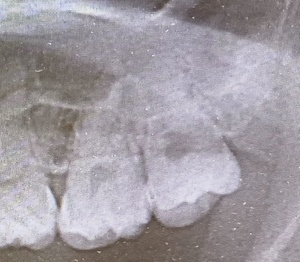

どうやって診断される?|検査・受診の流れを解説

歯科・口腔外科での診察方法

医師の視診で典型的な白斑や網目状の模様が観察されれば、口腔扁平苔癬と仮診断されることが多いです。

組織検査(生検)が必要なケースとは?

白斑が厚く、患部が硬い、出血しやすい

痛みが強く、潰瘍がある

がん化のリスクを排除したい場合

このような場合には粘膜の一部を採取する生体検査(生検)が行われます。

【がん化の危険性】口腔扁平苔癬は口腔がんになる可能性がある?

がん化リスクはどのくらい?

口腔扁平苔癬のがん化率は文献によって異なりますが、0.5~2%程度と報告されています。長期・重症病変や潰瘍形成のある例では注意が必要です。

観察・経過観察が必要な理由

病変ががん化している兆し(硬さ、色の変化、潰瘍化)が現れる場合があるので、定期的な診察と写真記録によるモニタリングが推奨されます。また自己チェック法として、鏡を使用して病変の変化を確認する習慣も有効です。